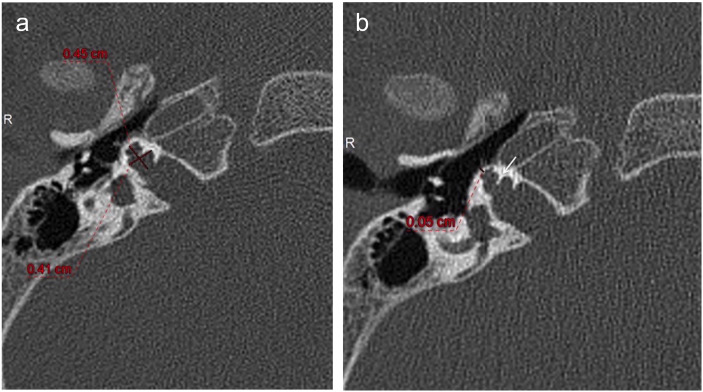

Results: All cases had bilateral IP-III anomaly, bulbous internal auditory canals (IACs), absent bony modiolus with preserved interscalar septa, intact cochleovestibular, and facial nerves. OC thickness was decreased in all cases compared to the control group (p<0.001). In XLD patients, the cochlea had decreased transverse dimension and increased height compared to the control group (p< 0.001). Five patients (38.4%) had bilateral cystic structures adjacent to the vestibule and/or semicircular canals (SCCs). Hypothalamus was thickened or had a lobular appearance in all cases (subtle in one). Additionally, hamartoma-like appearance of the hypothalamus was present in half.

Conclusion: XLD is a rare inner ear anomaly that is frequently associated with hypothalamic malformations. The OC thickness of IP-III patients appears to be decreased with accompanying decreased transverse dimension of the cochlea which could have implications in electrode selection during cochlear implantation. Cystic /diverticular lesions surrounding the vestibule and semicircular canals are also frequently seen but a rarely reported finding.